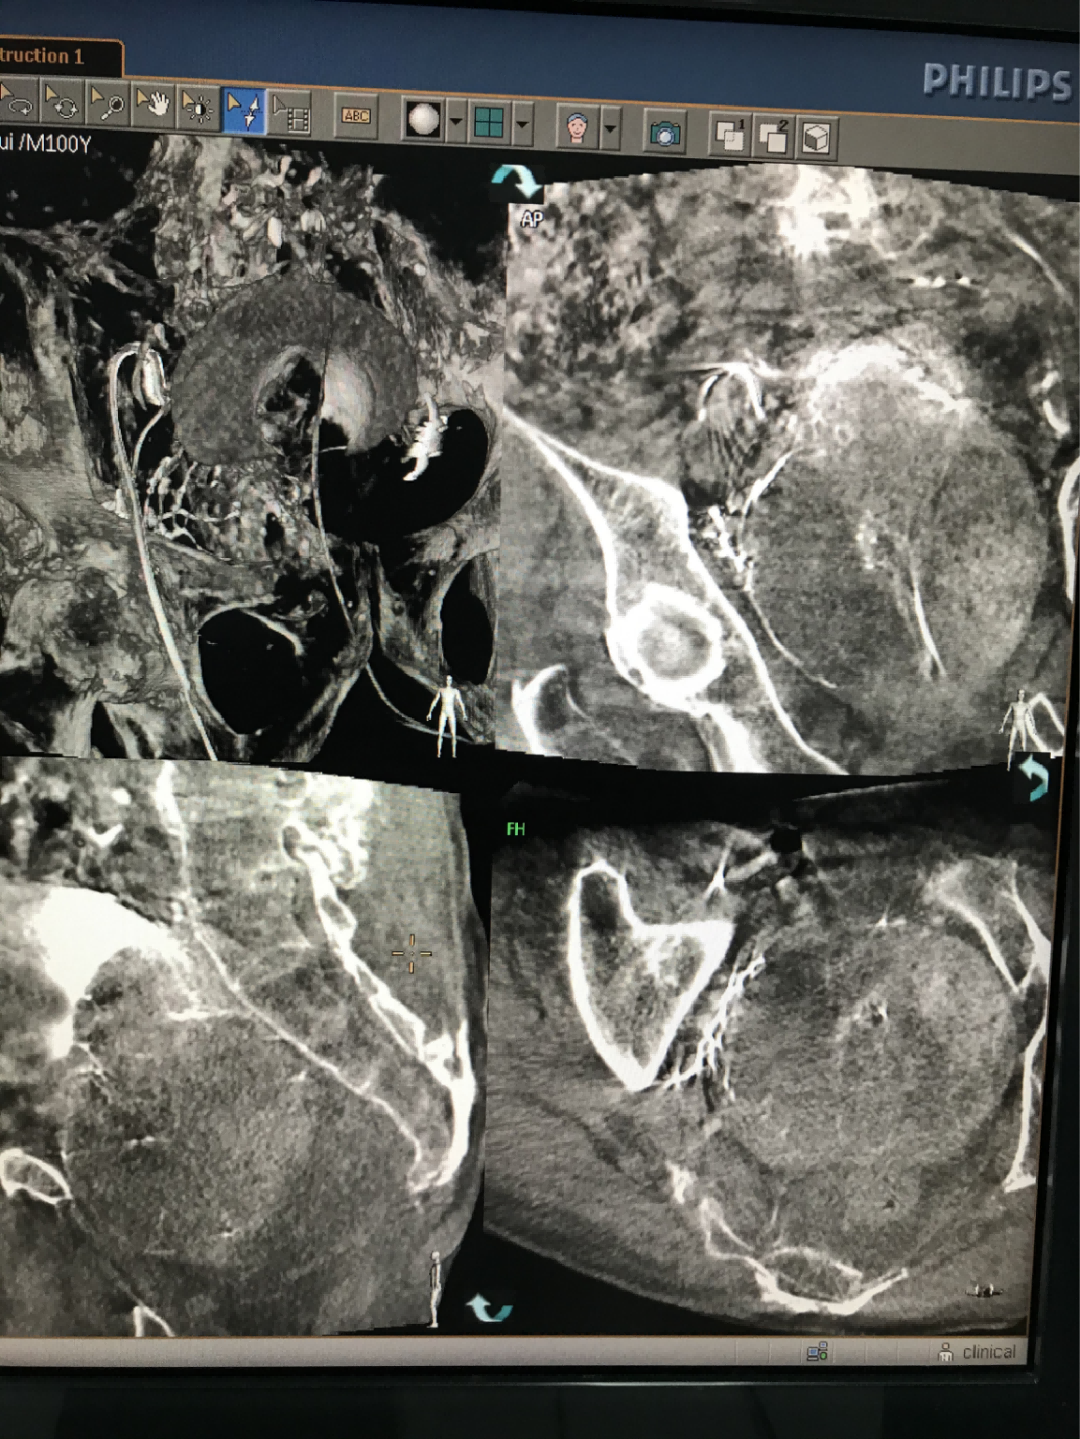

图:使用CBCT扫描避免误栓其他血管